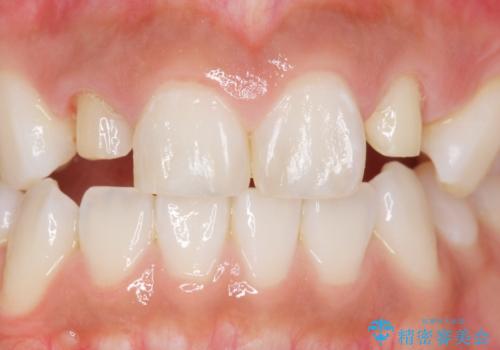

- 上の前歯の色と隙間を気にされ、来院された患者様です。

精査したところ、右上の側切歯(右上2)は神経が死んで変色しており、左上の側切歯と犬歯の間に2mm程度の隙間を認めました。

学生時代に舌側矯正をされており、通院が大変になり治療を途中でやめてしまったとのことでした。

矯正せずに早く治したいという強いご希望により、セラミッククラウンによる補綴治療(上顎両側2の2本)を行いました。